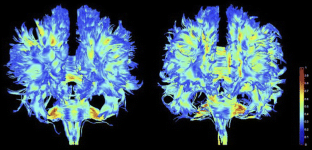

Fig. 1